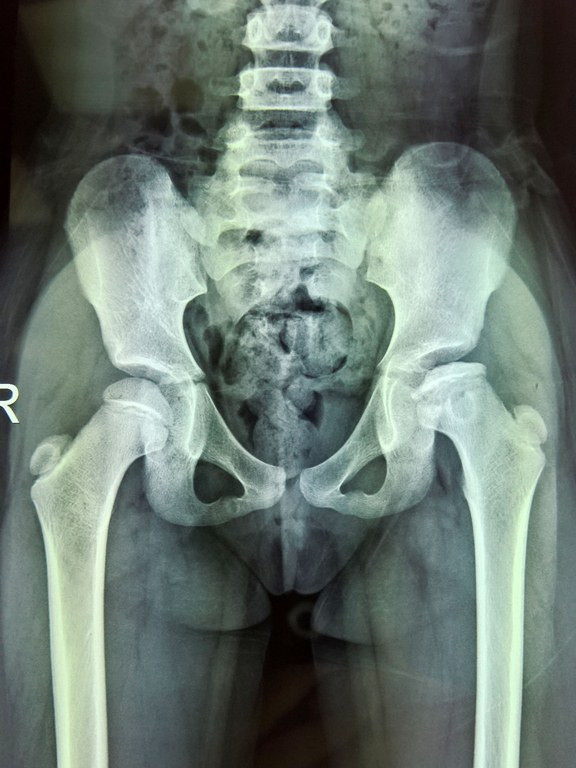

Ảnh chụp Xquang chỏm xương đùi bệnh nhân

Qua tìm hiểu, gia đình bé T đã quyết định đưa con đến khám tại khoa Chấn thương Chỉnh hình Nhi BV Đa khoa Xuyên Á và “tá hỏa” khi biết bé bị hoại tử chỏm xương đùi trái vô trùng kèm bán trật khớp háng bẩm sinh, chỉ định phẫu thuật để tránh biến chứng sau này.

Cũng theo BS Tiếp, sau khi thăm khám và kiểm tra cho bé T, các BS đã tiến hành phẫu thuật điều trị giúp làm rộng độ che phủ chỏm xương đùi, chỉnh hình ổ cối theo phẫu thuật Salter. Sau phẫu thuật, tình trạng bé đã ổn định, sẽ tháo bột sau 2 tháng, kèm tập vật lý trị liệu.